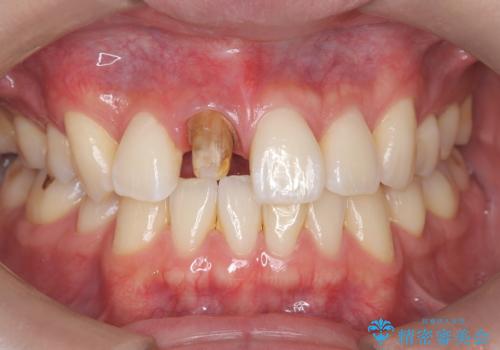

- 前歯の見た目が気になるを主訴に来院された患者様です。

根管の充填物も不十分だったため根管治療からやり直しオールセラミッククラウンで治療を行いました。

根管の中が空洞のままで被せ物と歯のきわも合っておらず適合が悪い状態でした。根尖部付近にはパーフォレーションリペア修復の痕がありました。バイオシーシーラーを使用しシングルポイント法で充填しました。空洞があると細菌が増える環境になってしまうので、根管治療からやり直し、緊密に充填しました。被せ物の見た目も大変満足していただけました。